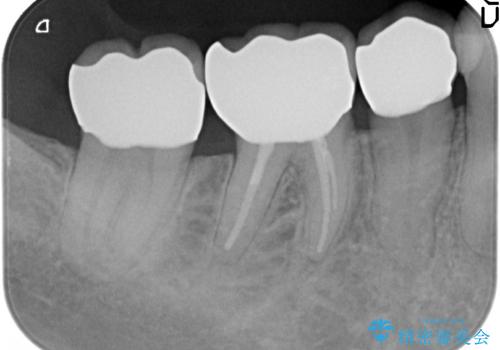

- 右下奥の銀歯3本をオールセラミッククラウンで治療した症例です。

右下6は失活(神経が死んでいる状態)していたため根管治療を行いました。